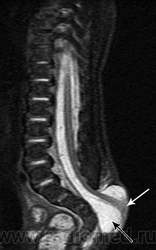

Терминальное миелоцистоцеле

Приложения:

3.cover_.giff20.medium._terminal_myelocystocele..giff21.medium._terminal_myelocystocele..giff22.medium._terminal_myelocystocele..gif